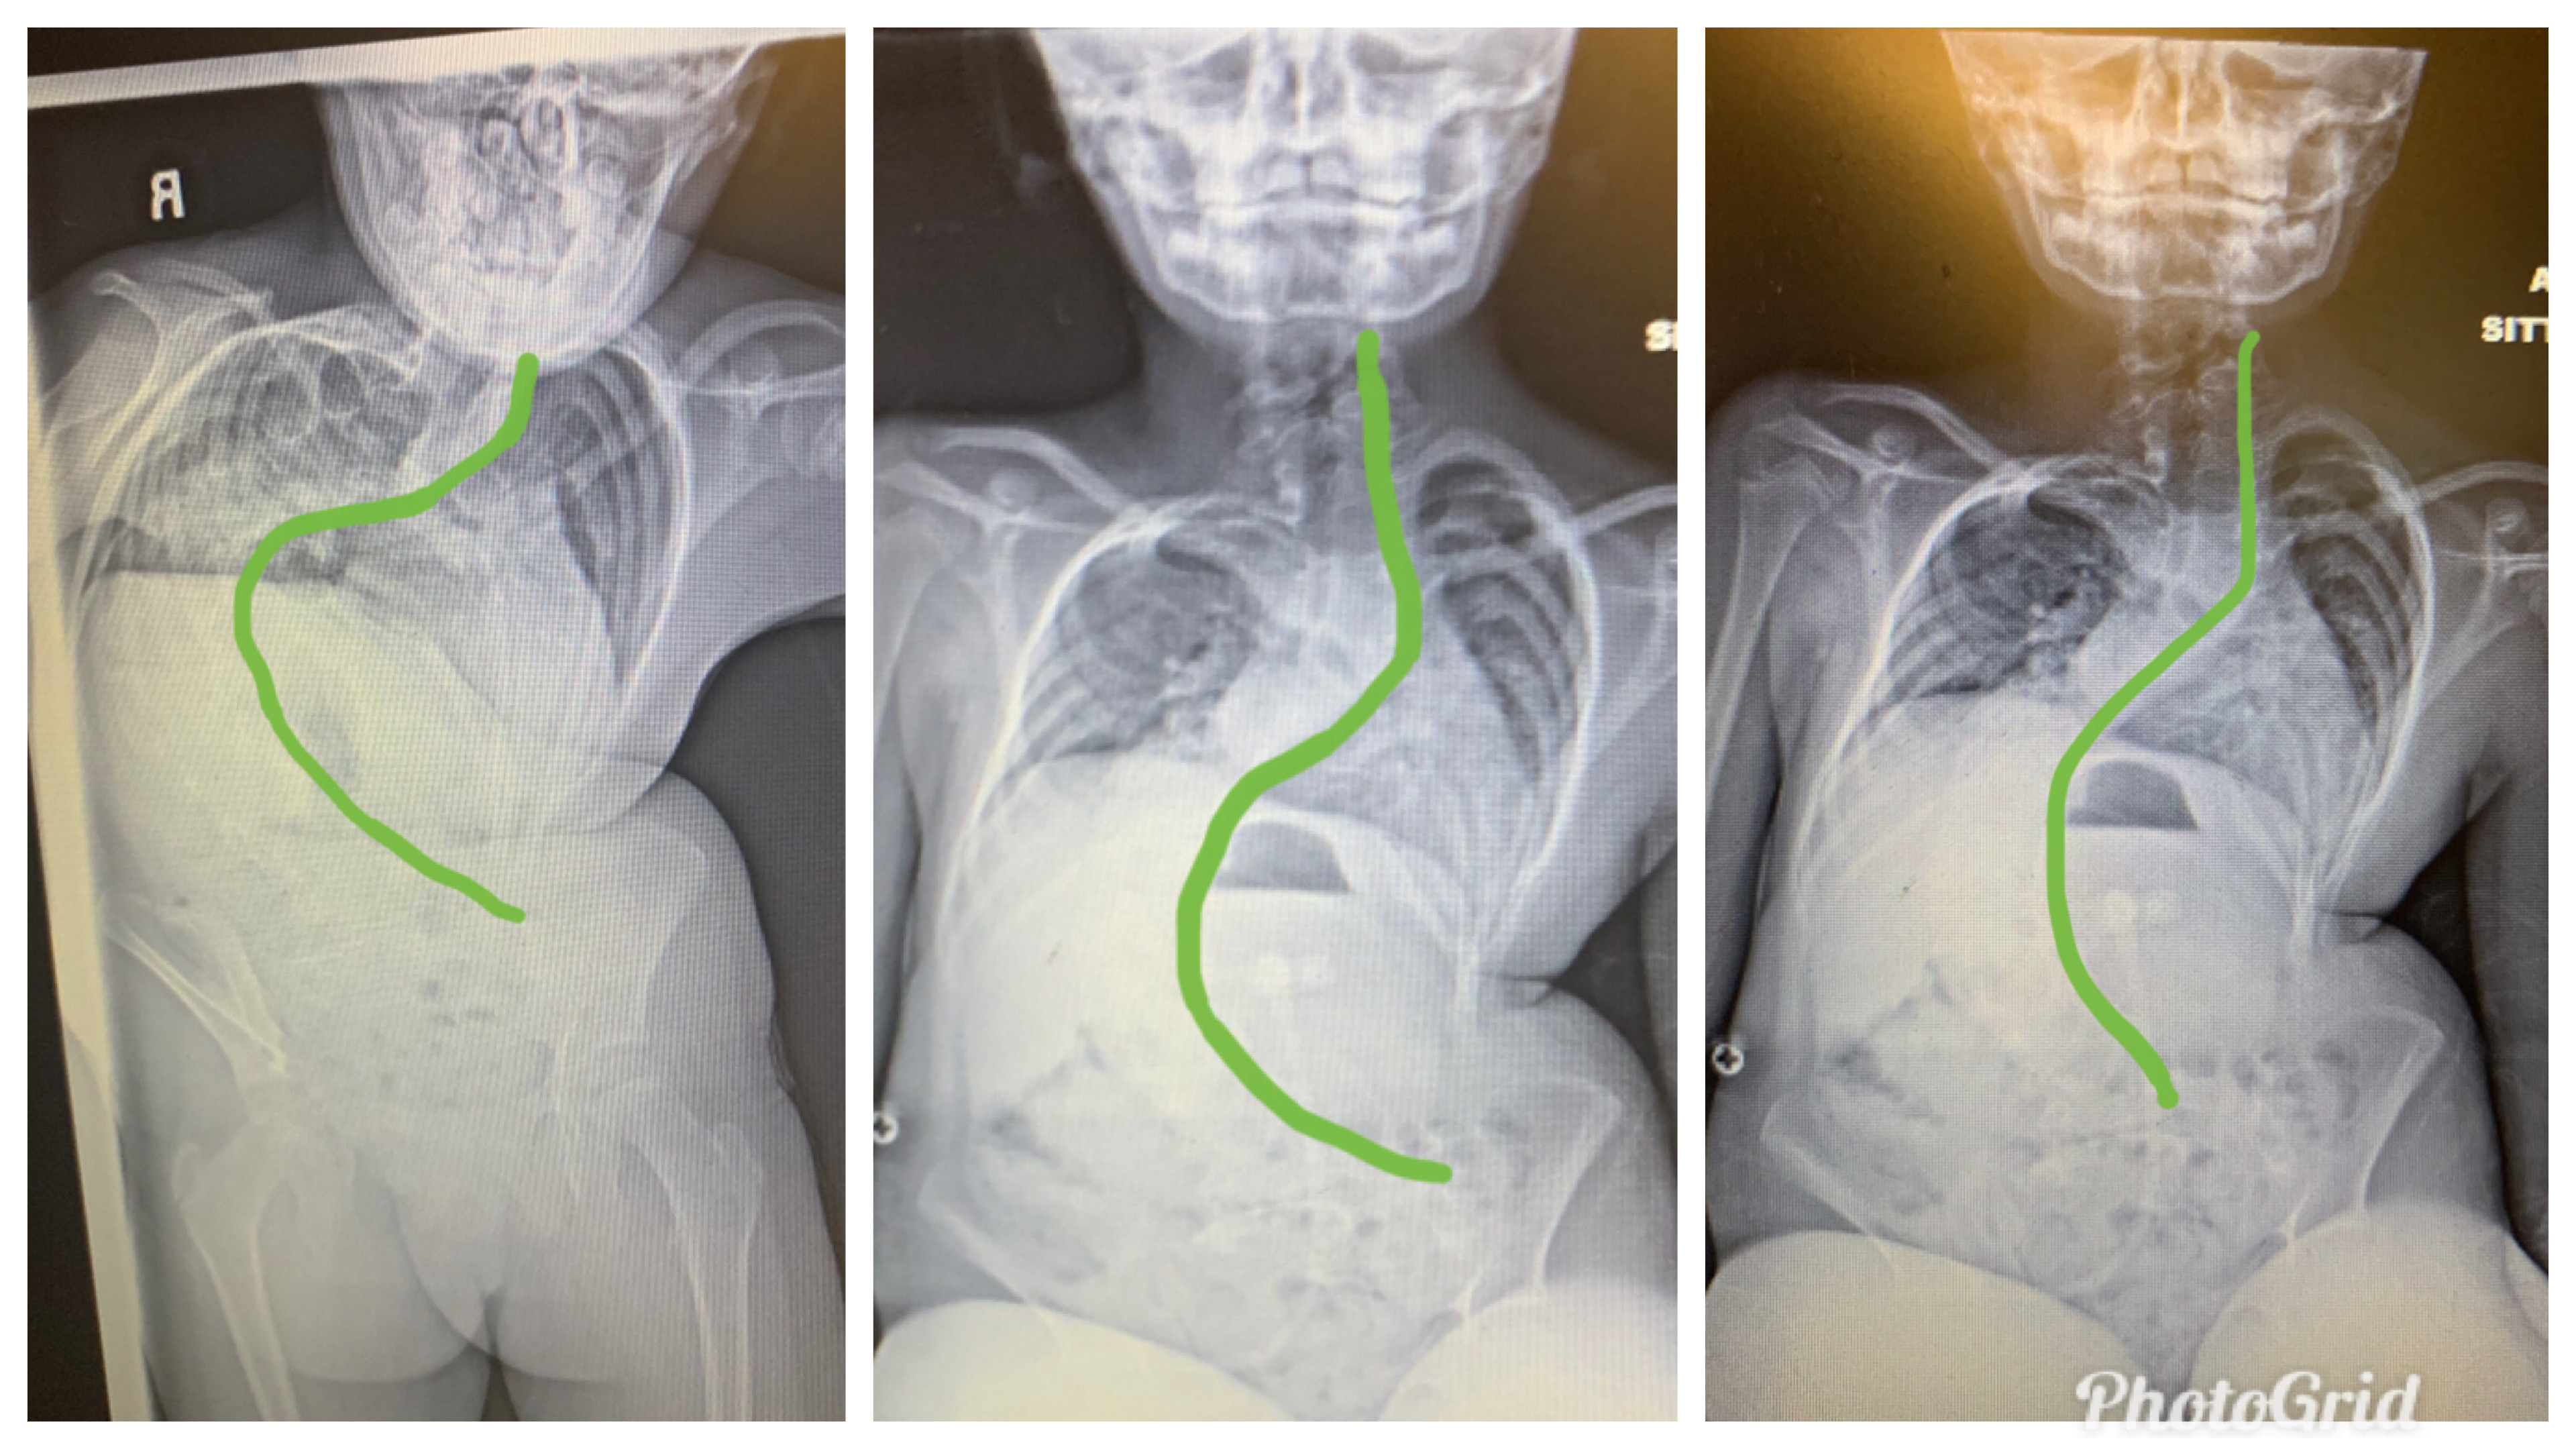

Immediately, noticing that she was “tugging” to breathe. The X-ray showed multiple skeletal abnormalities, including scoliosis, butterfly-shaped vertebrates, a small chest wall, fused, and missing ribs. Despite the poor prognosis, Tenleigh’s parents did not give up hope. After taking research into their own hands, the twenty and twenty-one-year-old parents found hope thirteen hours away from home at the Children’s Hospital of Philadelphia (CHOP).

January 01, 2020, the family began their undetermined extended stay at Boston Children’s Hospital. Furthermore, Tenleigh had the halo application applied to her skull with four pins on January 07, 2020, spending the next month attached to a weighted pulley system to lengthen her spine naturally. On February 06, 2020, Dr. Emans removed the halo and implanted two customized growing rods. Overall, Tenleigh’s Cobb Angle (spinal degree of curvature) improved from approximately 120-130 degrees to 60-70 degrees! Immediately, Tenleigh felt relief. Additionally, she could perform her activities of daily living (ADL’s) better than before and continued to impress the doctors by recovered at lightning speed! After 59 days away from home, the family finally returned home on February 28, 2020.